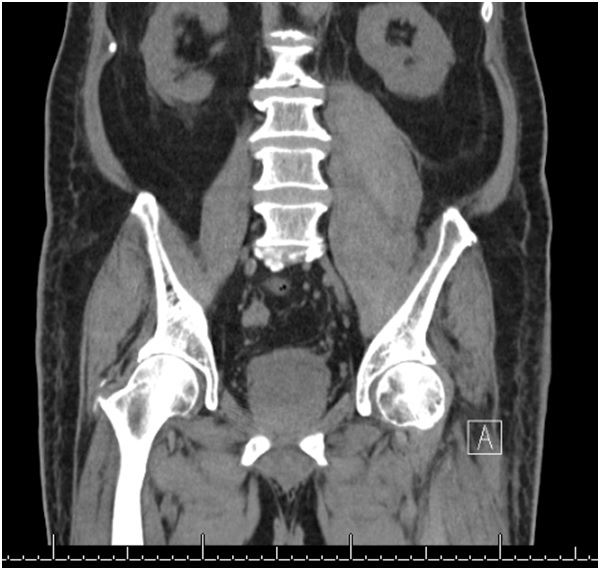

Case Presentation: 82-year-old man on chronic Warfarin presented for evaluation of spontaneous right lower extremity swelling with bruising. Workup showed hemoglobin of 9.5 g/dL, platelet of 286 K/µL, PT 47.4 seconds, INR 5.0, and PTT > 200 seconds. CT of abdomen and leg revealed intra-abdominal hemorrhage and subcutaneous hematoma of the right leg. Within the first 24 hours of hospitalization, patient had drop of hemoglobin down to 6.4 g/dL from acute hematochezia. Patient required multiple units of red cells and fresh frozen plasma along with vitamin K. Spontaneous bleeding initially was attributed to supratherapeutic INR level. However, further workup revealed incompletely corrected PTT mixing study with on ongoing prolonged PTT, concerning for acquired factor inhibitor. FVIII assay was 2% with significant inhibitor titer of 92 Bethesda Unit (BU). Patient was started on Prednisone 1mg/kg daily and Cyclophosphamide 1 mg/kg daily to eradicate inhibitor. Patient underwent malignancy workup that revealed a 2.6 cm anterior mediastinal mass concerning for thymoma. Hospital course was further complicated by development of left iliopsoas intramuscular hematoma. He required treatment with recombinant activated fVII to act as a bypassing agent and also with recombinant fVIII for hemostasis of iliopsoas bleeding. Immunosuppression resulted in increasing fVIII level and decreasing inhibitor titer (92 BU –> 13 BU –> 1.3 BU). Patient required prolonged rehabilitation due to severe weakness and sensory loss from iliopsoas hematoma and femoral nerve compression.